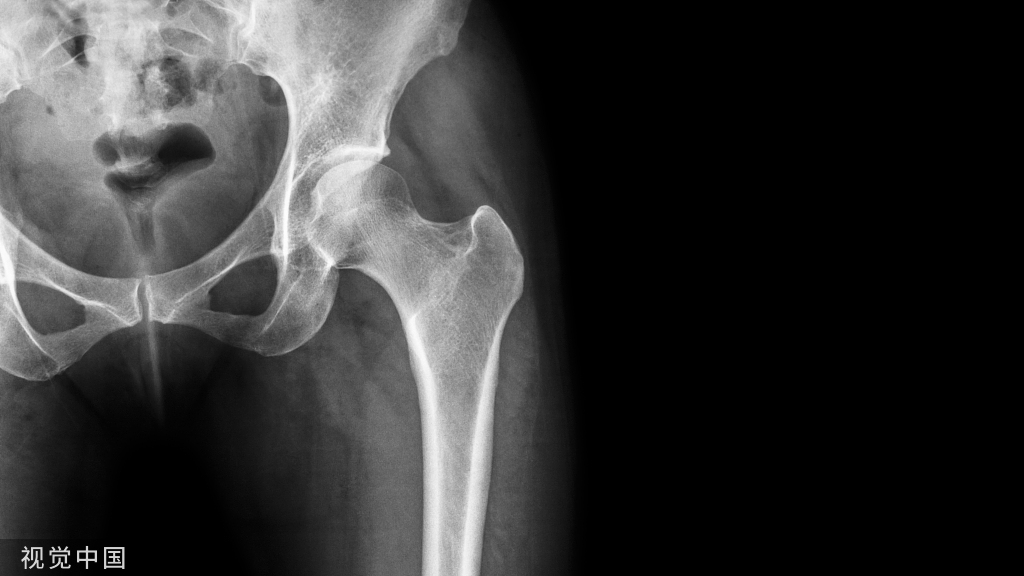

一、弹性髓内钉的应用原理以股骨干中段斜形骨折为例:骨折近、远端肌肉收缩产生轴向应力R,根据力的合成与分解平行四边形法则,平行四边形的对角线表示合力,两个邻边为分力;合应力R分解出两个分力即压应力C剪应力 S,压应力促进骨折愈合、剪应力妨碍愈合;剪应力S的分力L使骨折远端向外移位,导致侧方移位或成角畸形(图1)。

将第一枚弹性钉预弯成“C”形,经股骨干远端外侧皮质逆行打入髓腔,依靠其弹性在远端皮质(入钉点)、断端髓腔(“C”形的顶点)和近端干骺端(钉尖)形成三点固定;骨折端向外的弯曲应力大于肌肉收缩形成的轴向压应力,因此产生向内的成角畸形(图2)。

第二枚弹性钉的直径、预弯的“C”形弧度与第一枚弹性钉相同,并在同一平面由内侧皮质逆行打入后也形成三点接触,力的大小与第一枚弹性钉相等而方向相反。两枚“C”形弹性钉的凹面相对,弧形的顶点位于骨折端,这种对称排列的固定模式、弹性钉内在的弹性以及周围软组织框架,使骨折端的应力达到平衡,有效地抵抗了弯曲应力,将剪应力转化成垂直的张应力 T 和压应力 C,维持了复位后的稳定,有利于骨折的修复愈合[3](图3)。